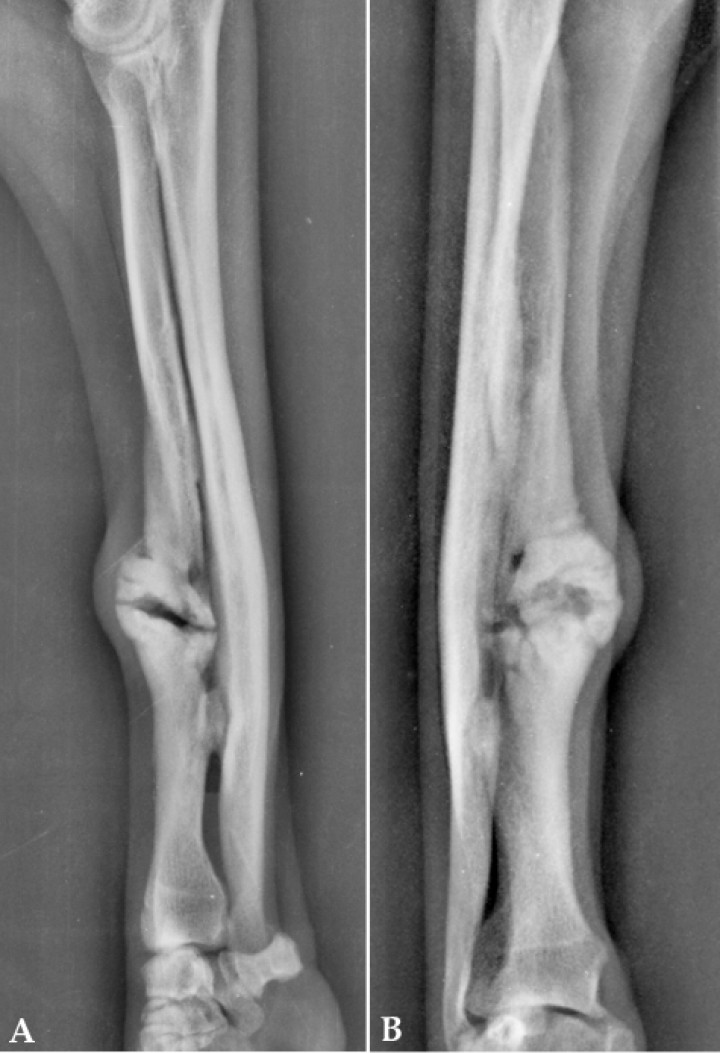

El perro acudió de nuevo a consulta 4 meses después de la última visita con una cojera de 5/5 del miembro afectado. A la palpación, presentaba dolor severo en el foco de fractura, que apenas se dejaba palpar, y abultamiento apreciable visualmente, con inflamación de los tejidos blandos adyacentes. La rigidez articular del carpo seguía siendo evidente, sin mejoría en el PROM. Las imágenes radiológicas revelaron la formación de una no unión hipertrófica (Fig. 4).

<p> (<strong>A</strong>) Proyección radiológica mediolateral. (<strong>B</strong>) Proyección radiológica craneocaudal. Se puede observar la no unión hipertrófica (día 508).</p>

(A) Proyección radiológica mediolateral. (B) Proyección radiológica craneocaudal. Se puede observar la no unión hipertrófica (día 508).